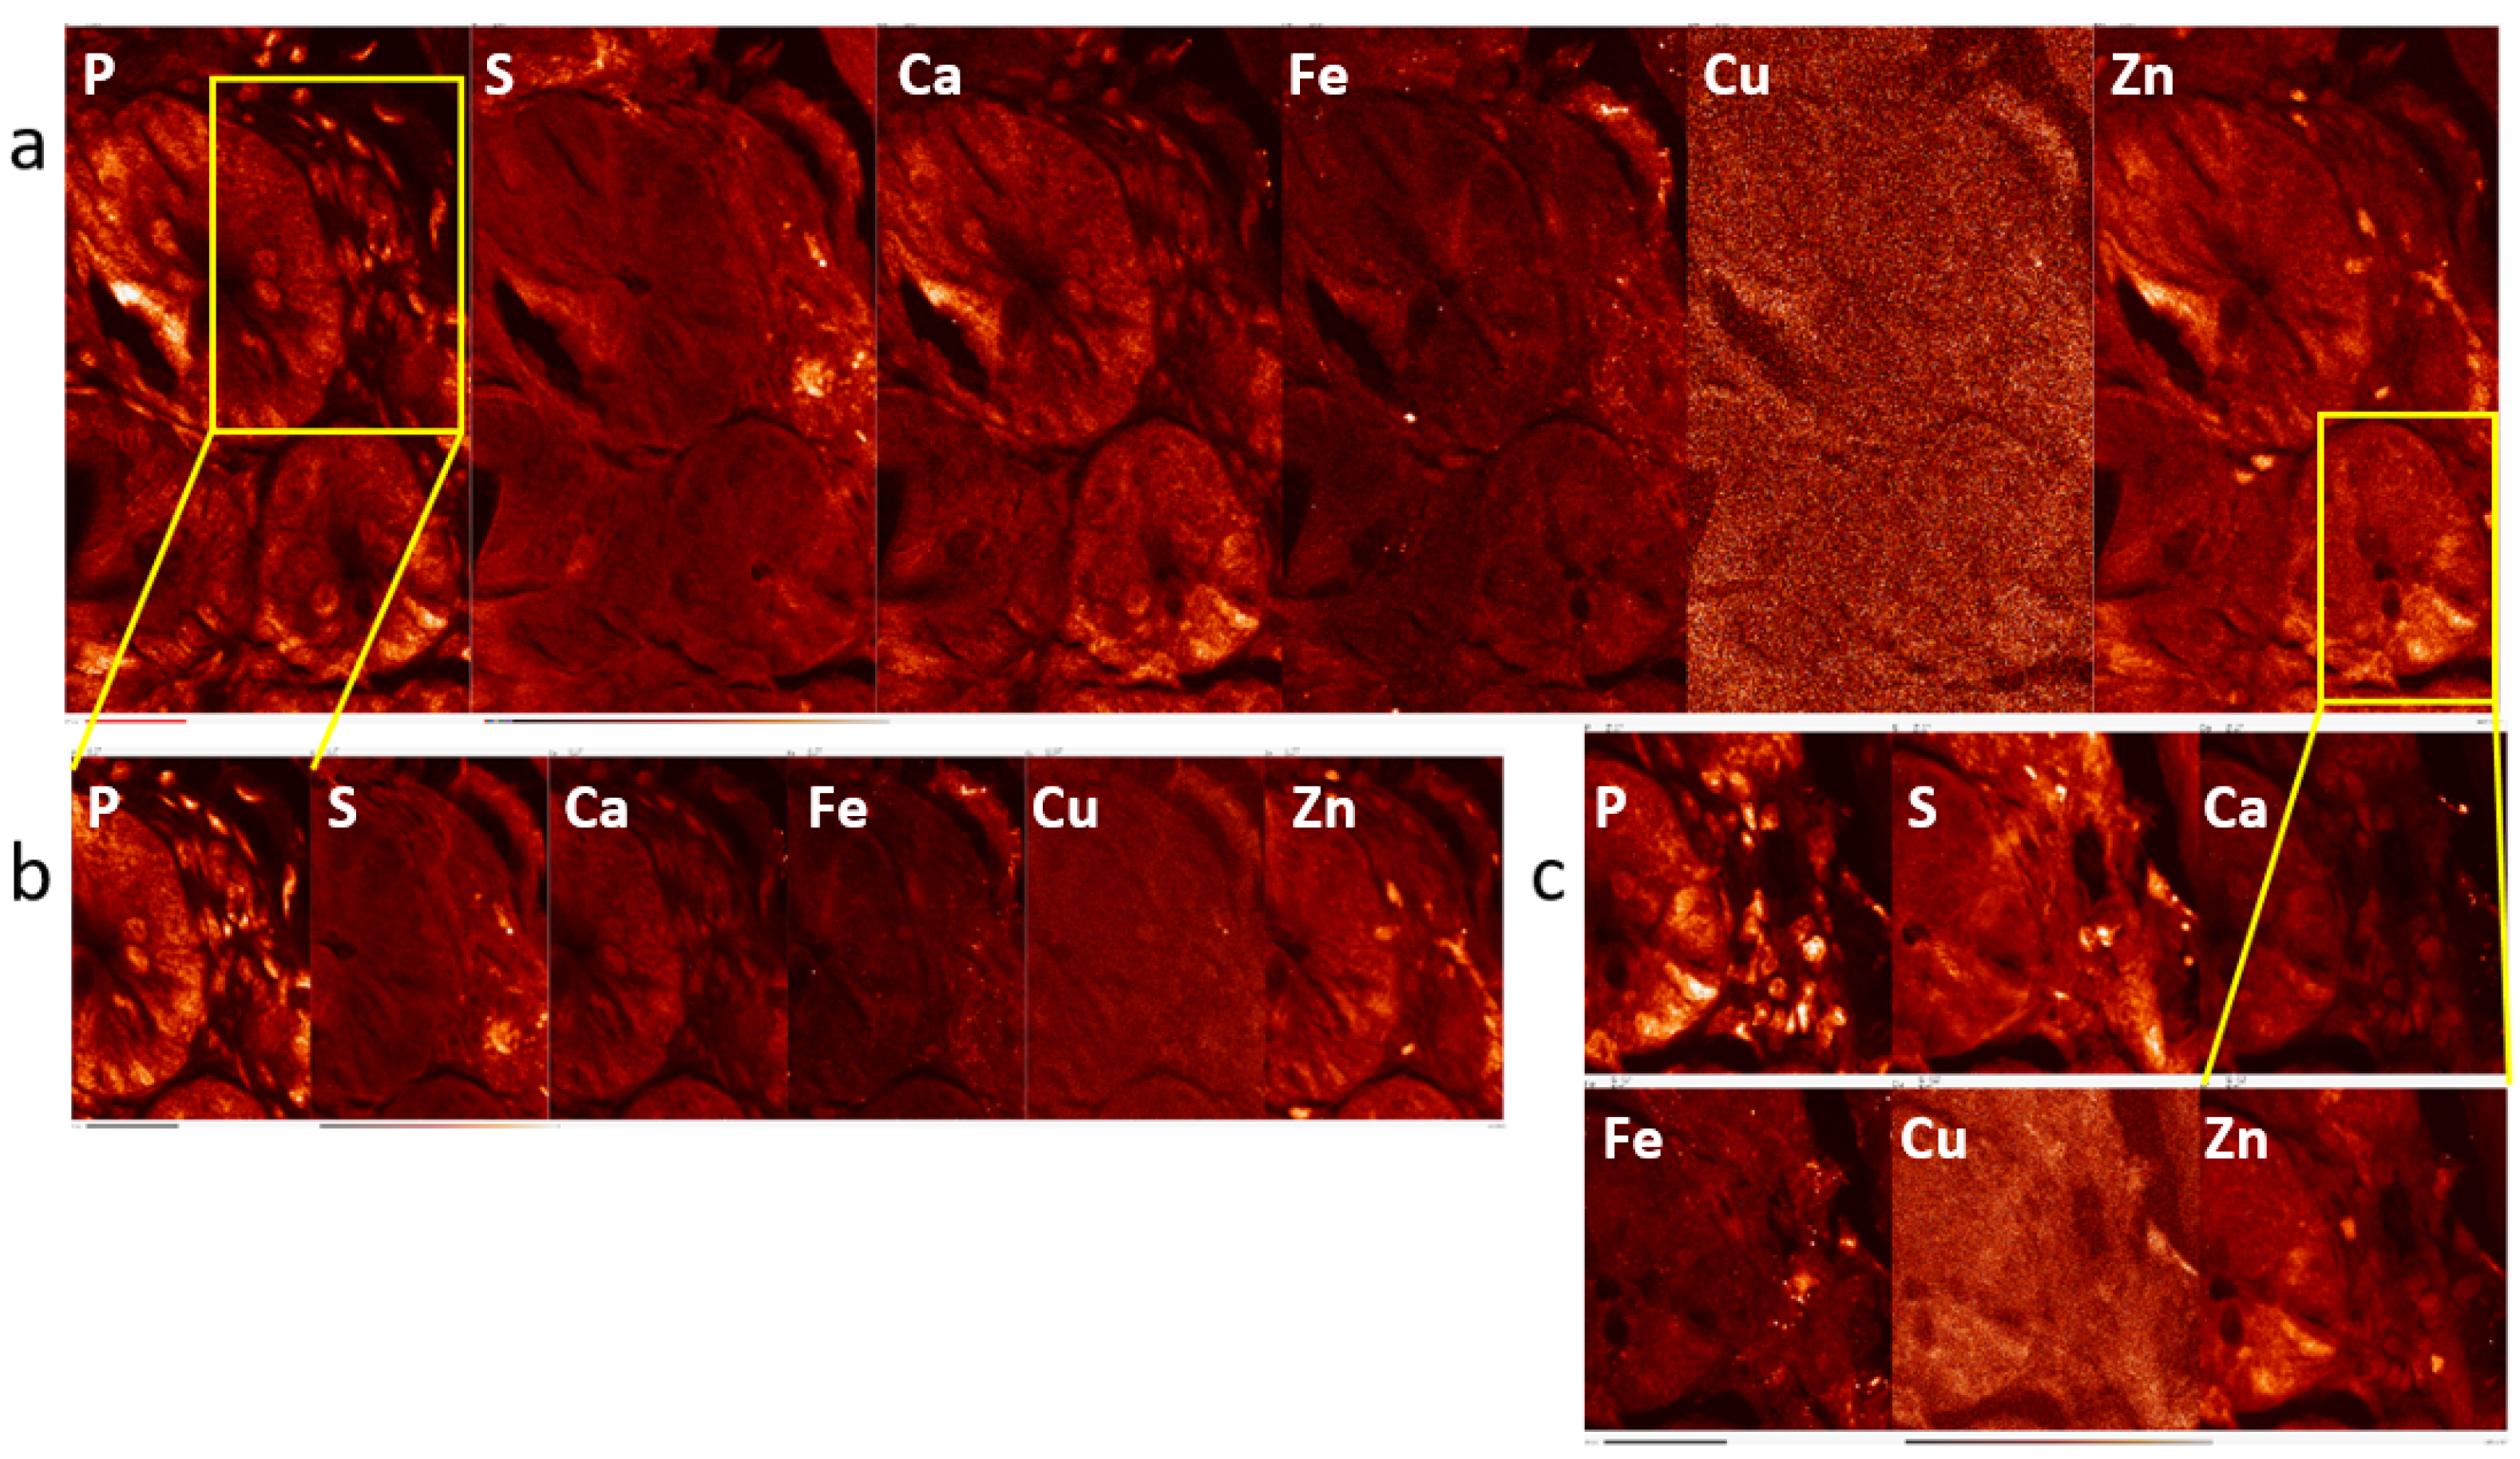

2.1. Elemental Maps of Control and Irradiated Mouse Intestine Samples